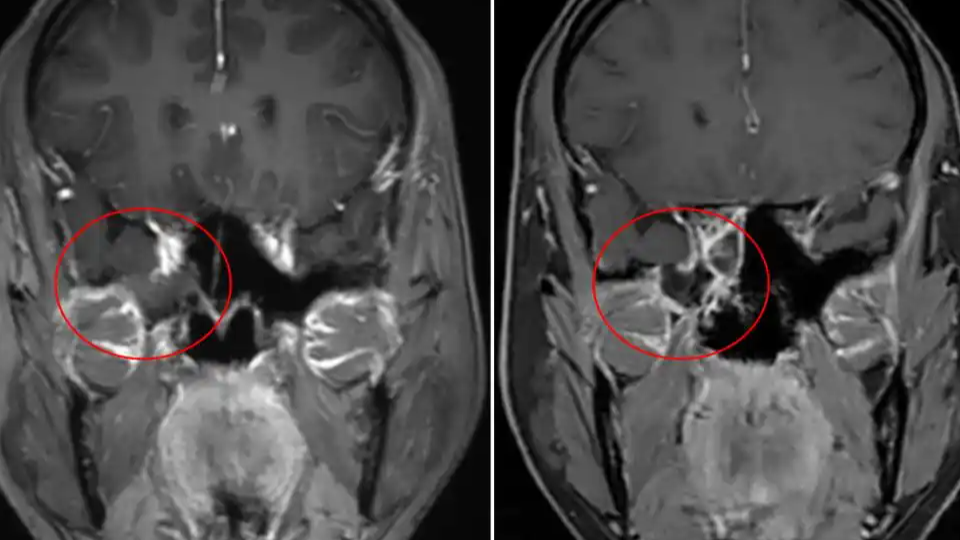

• 女子反复流涕竟是脑子“漏了”

春夏交替之际,鼻炎、呼吸道感染等疾病多发,广东39岁居民罗女士因此没将自己反复流涕的情况太当回事,直到20天后她在耳鼻咽喉头颈外科确诊患上脑脊液鼻漏。专家提醒,脑脊液鼻漏可导致颅内感染风险、颅内低压、脑膜脑膨出等严重危害,一旦确诊,应尽早手术。